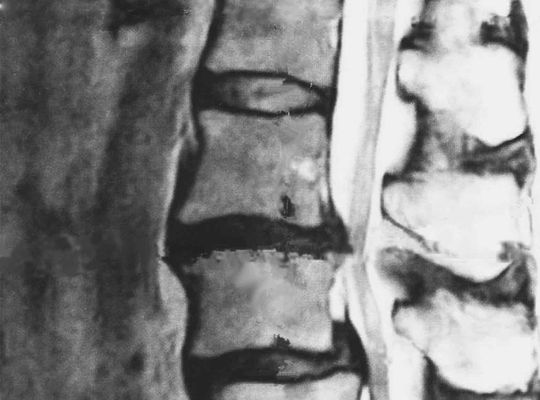

• 脊柱管狭窄症の腰痛にオススメ整体院!

FROM 慢性腰痛専門整体院TOKI       今回は   当整体院に来られる患者様の率で   一番高い   脊柱管狭窄症を   当院では ...

• 病院で行う脊柱管狭窄症の手術の中身とは?手...

FROM 慢性腰痛専門整体 整体院TOKI       今回は ストレッチとかリハビリの 話ではなく皆さんが気にしている 脊柱管狭窄症の手術についての...

• 脊柱管狭窄症は2種類あるってしってましたか?...

FROM 慢性腰痛専門整体 整体院TOKI           今日は 久しぶりの 投稿になりました。         大変申し訳ありません...